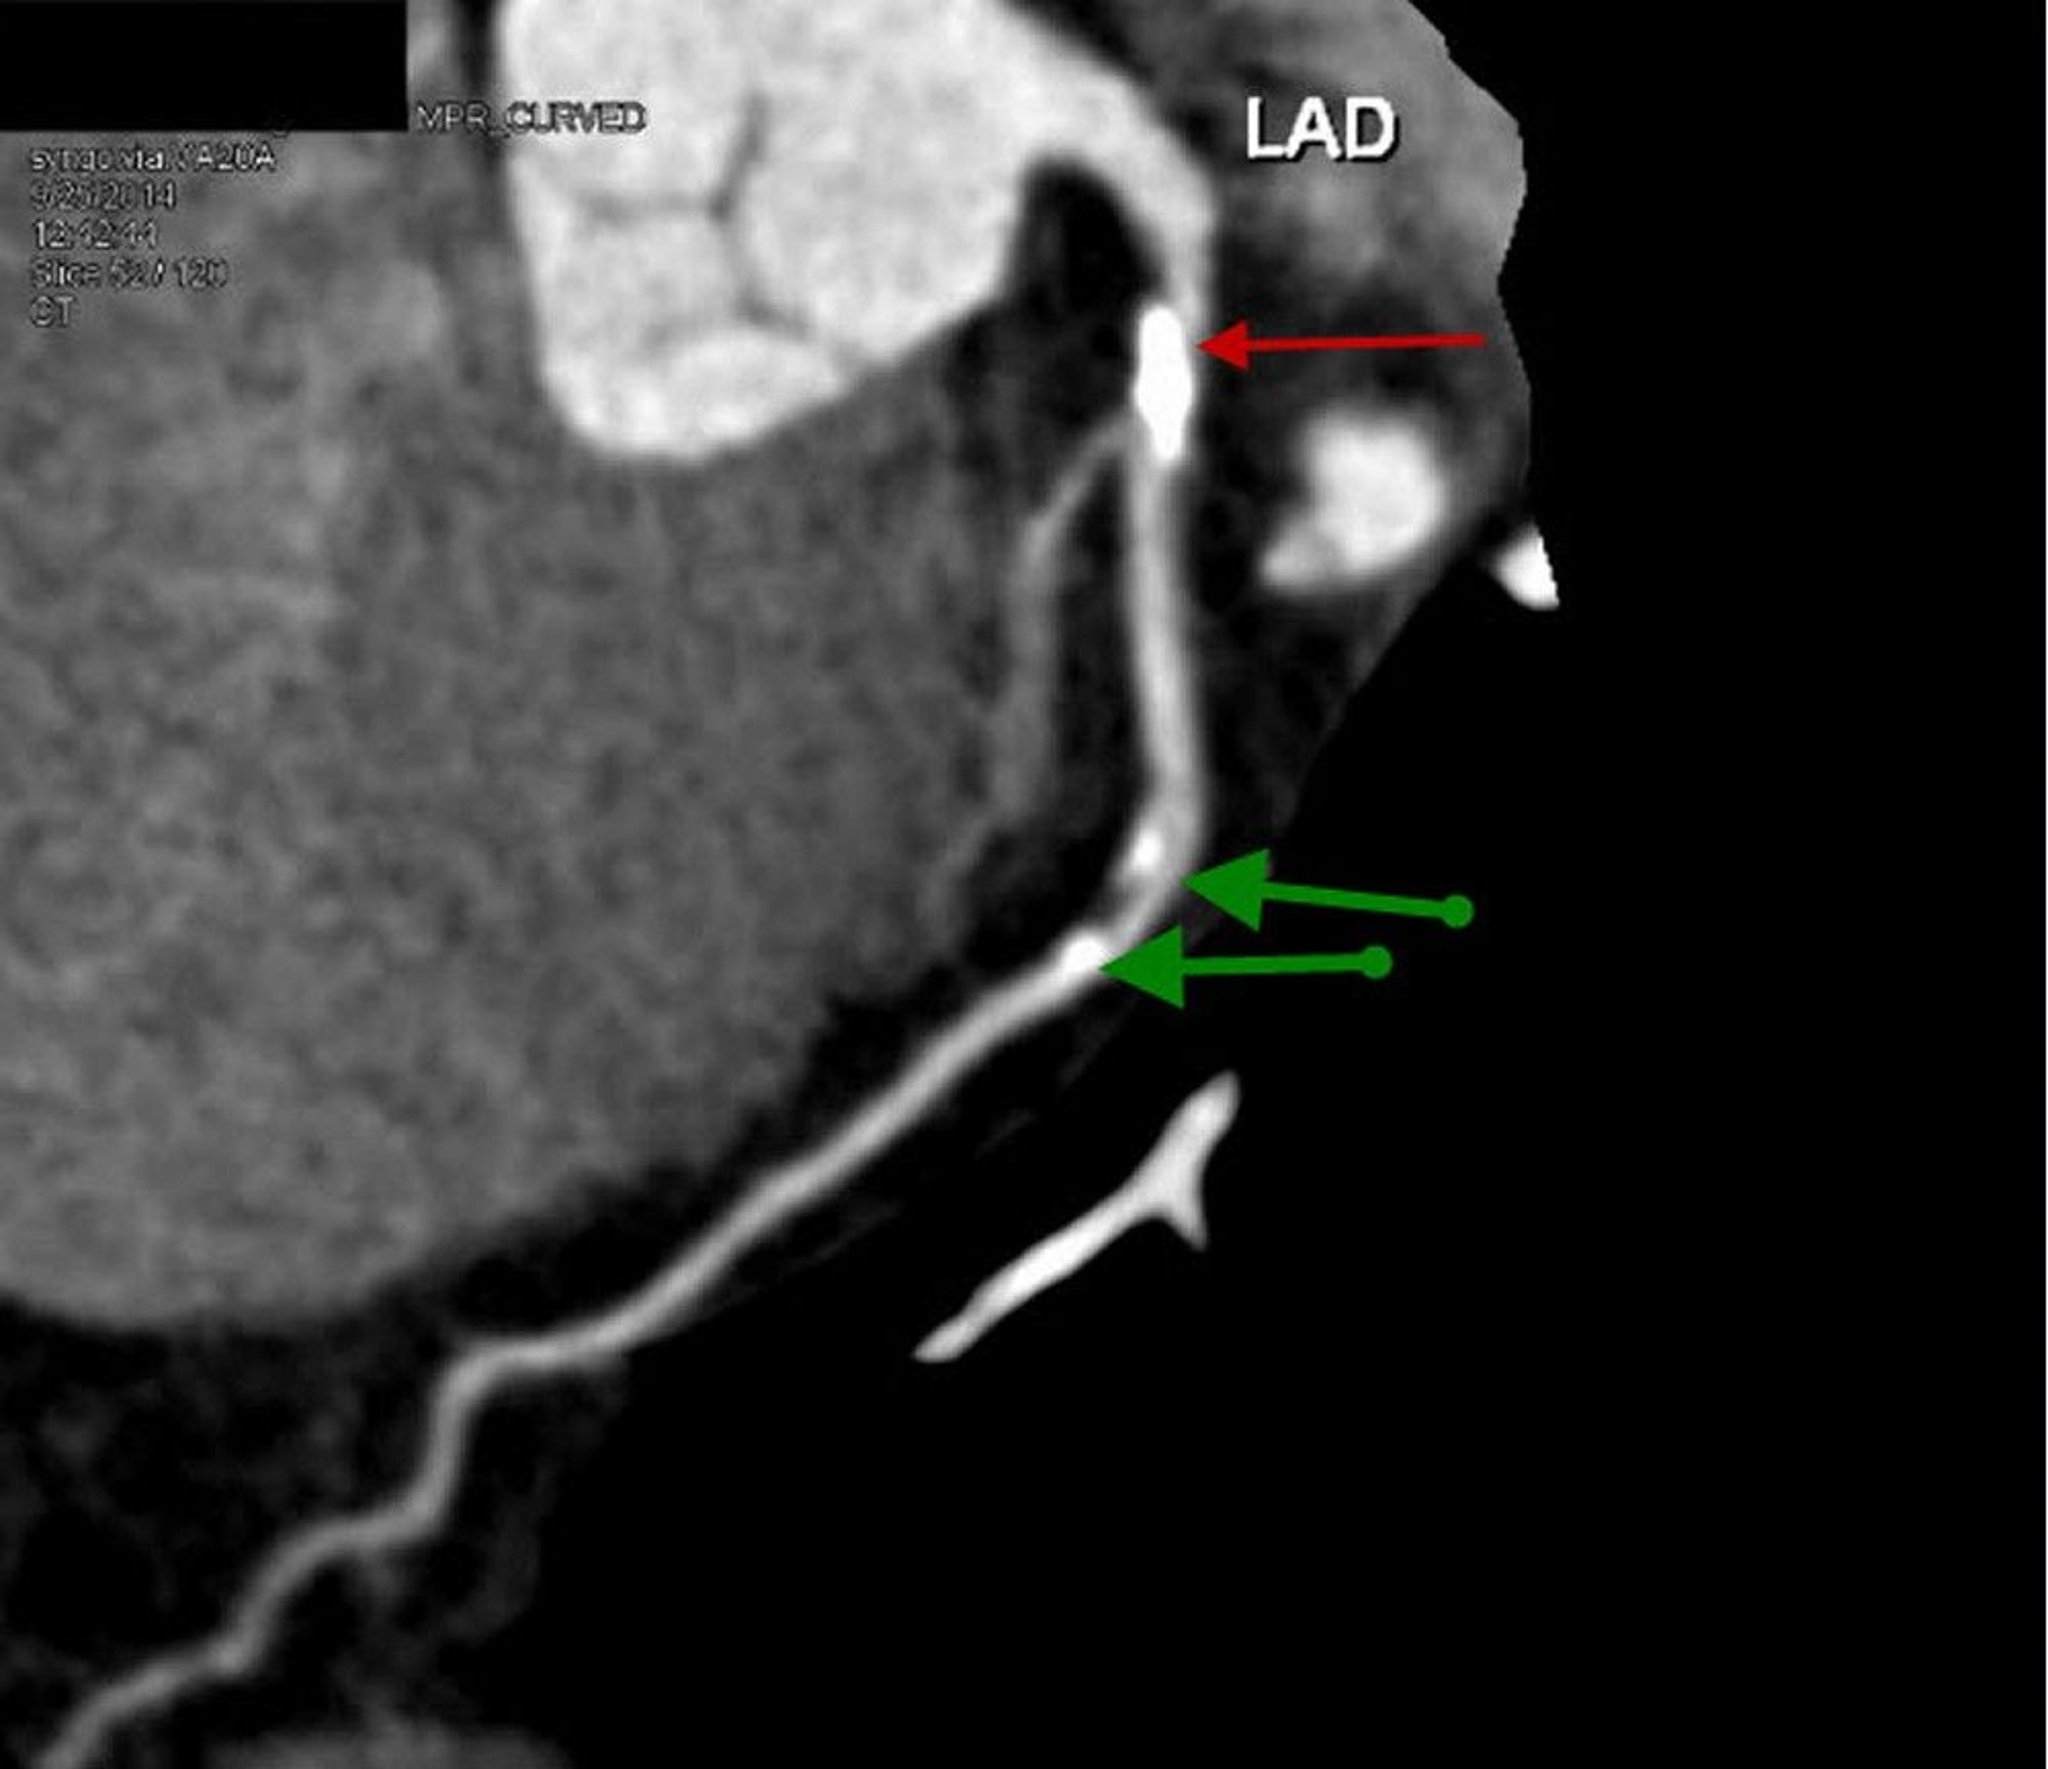

Contrast CT Showing Coronary Artery Disease

This contrast CT shows a reconstructed sagittal view of proximal left anterior descending artery with prominent calcified plaque and 70% stenosis (red arrow). Mid LAD shows mild stenosis of 20–30% (green arrows).